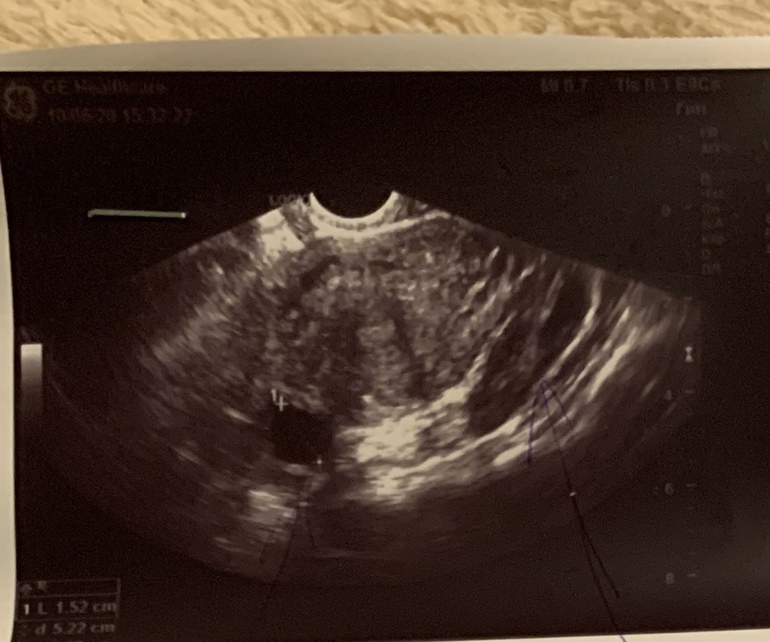

А это через день та же «двухкамерная киста»